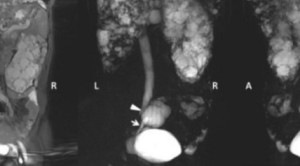

-   Perbandingan Efikasi Terapi Farmakologi Pasien Dewasa Dengan Penyakit Ginjal Polikistik Autosomal Dominan: Tinjauan Sistematik dan Meta-analisis Jaringan Dari Percobaan Acak Terkontrol - Telaah Jurnal Alomedika Perbandingan Efikasi Terapi Farmakologi Pasien Dewasa Dengan Penyakit Ginjal Polikistik Autosomal Dominan: Tinjauan Sistematik dan Meta-analisis Jaringan Dari Percobaan Acak Terkontrol - Telaah Jurnal AlomedikaComparative Efficacy of Pharmacological Treatments for Adults With Autosomal Dominant Polycystic Kidney Disease: A Systematic Review and Network Meta-Analysis of Randomized Controlled...(Baca Selengkapnya)